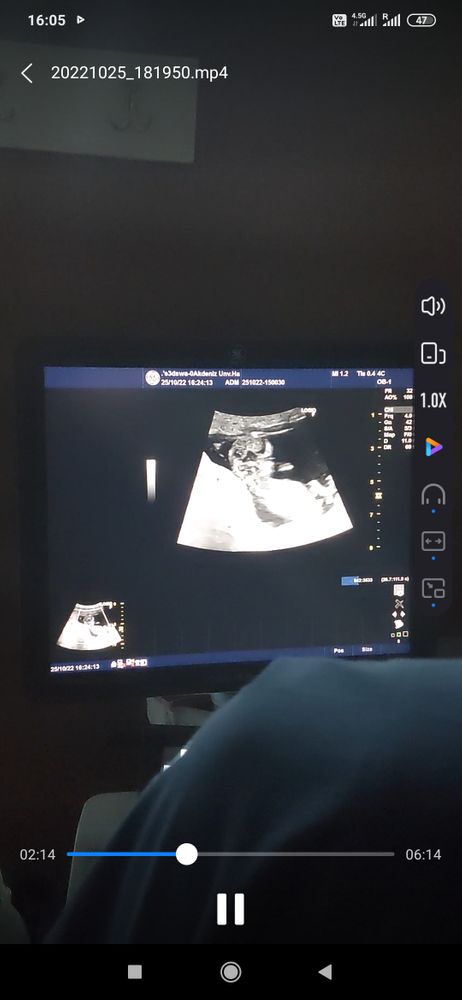

Пол ребенка в 12 недель и 6 дней.

Не тот ракурс. Так как у вас скриншот, смотрят с 16 недель. А пока и к мальчика и у девочки вид одинаковый

Маргарита, нормально все там с ракурсом, малыш боком лежит и видно половой бугорок

Маргарита, видео тоже есть, но мне показалось, что это самый удачный ракурс🤷